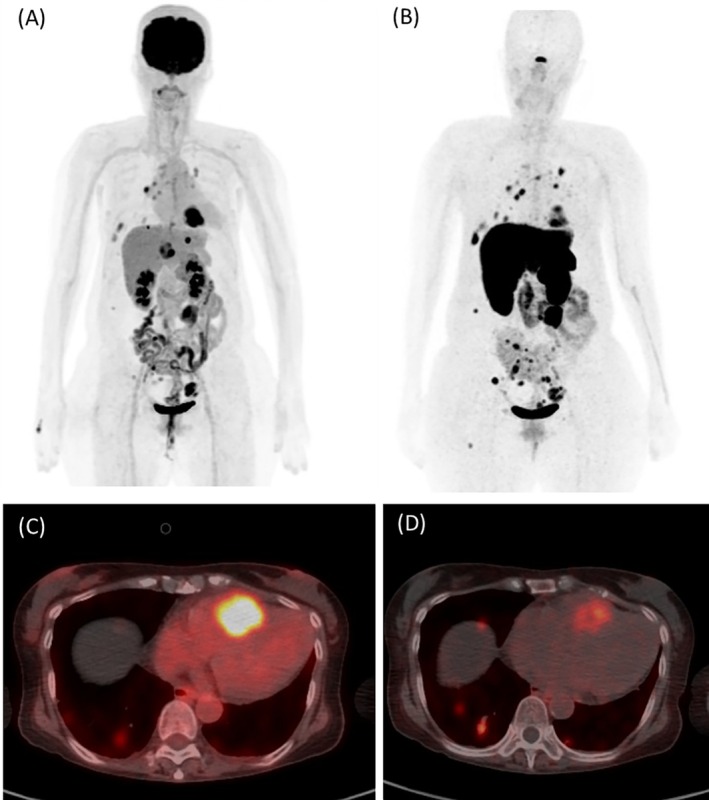

Kussmaul's Sign Provoked by Intracardiac Metastasis of Endometrial Neuroendocrine Tumor.